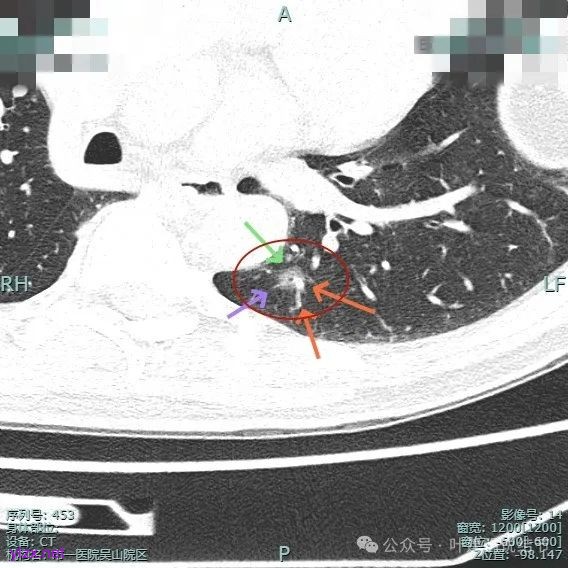

主病灶实性成分明显,表面有毛刺,边缘不平毛糙;次病灶密度纯且淡,轮廓清楚。

血管进入扭曲,毛刺明显,整体轮廓清,灶内小空泡征。

主病灶血管进入,灶内空泡,表面浅分叶,整体轮廓较清。

2、手术问题:由于主病灶不纯,血管进入与增粗明显,随访是有风险的,应该考虑手术切除。而若主病灶要切除,那么次病灶离它这么近,应该也要考虑一并切除,不然一是只切主病灶后若次病灶刚好位于切缘处,以后观察有无进展困难,二是以后若仍考虑手术,增加难度。从连续层面看以,主病灶位于后基底段靠近背段处,单纯后基底段切除切缘可能不太够;次病灶则靠近外基底段,如果单纯切除后基底段也不安全。经过科室讨论,意见是可以考虑背段加后基底段切除,后基底段与外基底段之间还要往外基底段侧多切过去点。或者后基底段切除,但离断段间平面时向背段侧扩大切除一部分,往外基底段侧也扩大切除一部分。如果切除基底段,还要往背段切过去点,那下叶余下也不多了。手术方式比较纠结。